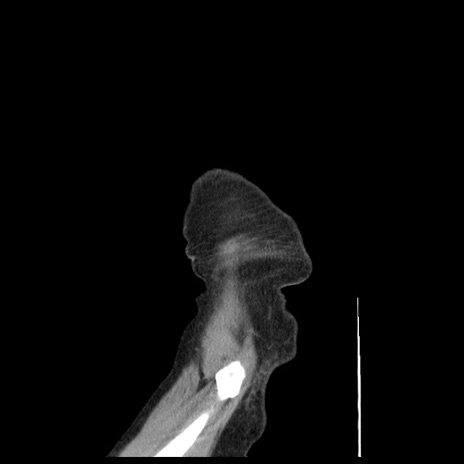

症例1(矢状断像)

【症例】80歳代女性

【主訴】腹痛

【現病歴】8時間前から腹痛あり来院。

【既往歴】糖尿病、脂質異常症、子宮体癌にて子宮全摘術

【身体所見】意識清明・会話良好だが腹痛で苦悶様、全腹部にわたって反跳痛と圧痛あり

【データ】WBC 13600、CRP 0.14、LDH 224、CK 90